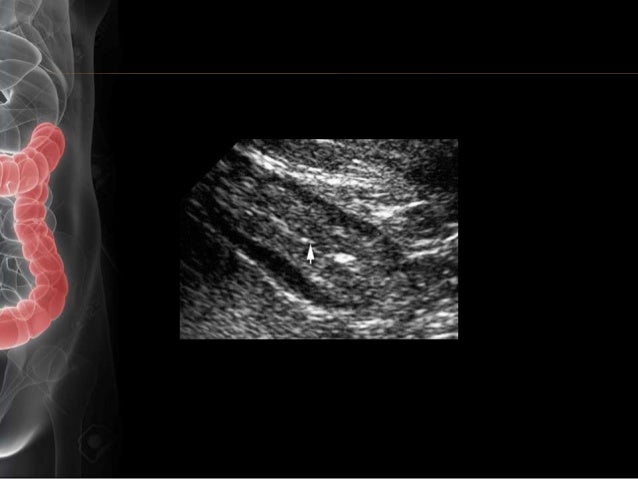

Vascular Injury Following Pyloric Dilation: Unusual Cause Of ...

Vascular Injury Following Pyloric Dilation: Unusual Cause of Ischemic Colitis Brian P. Riff, MD1, Cary B. Aarons, MD2, Endoscopic dilation of non-malignant pyloric stenosis has shown to be a safe and effective treatment option for ... Fetch Doc